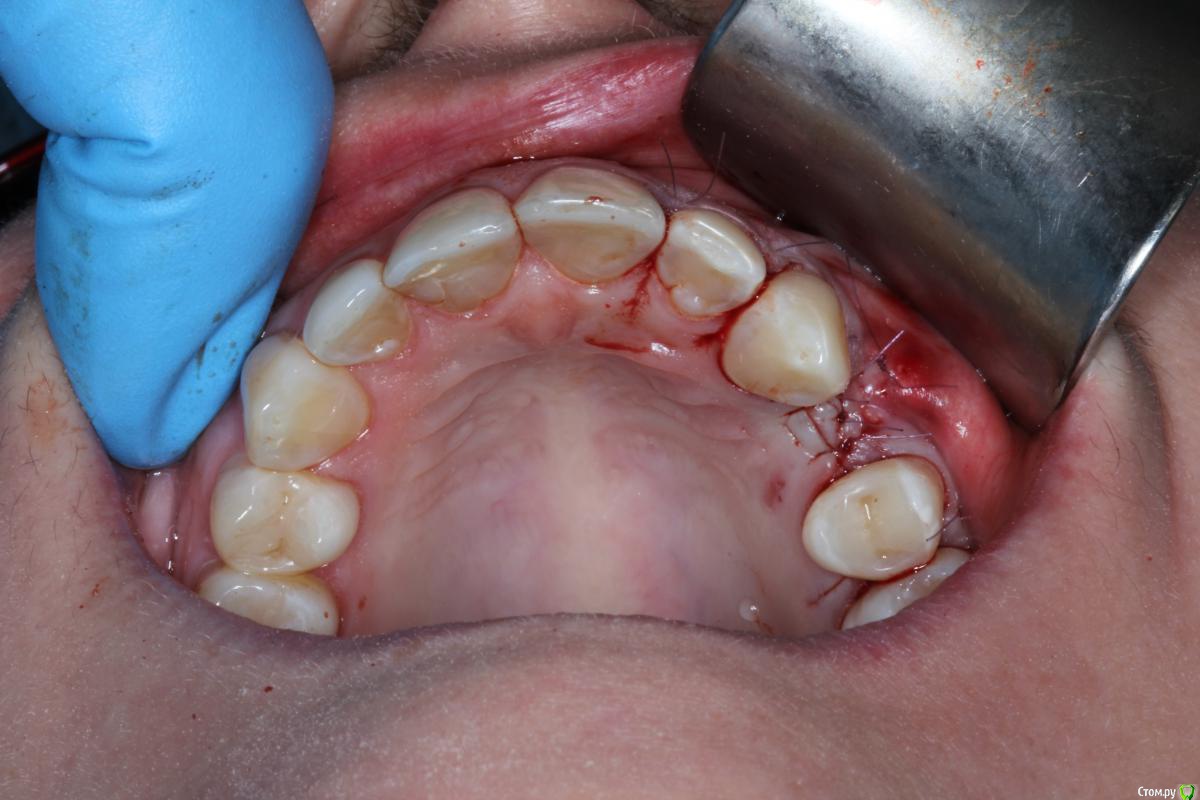

Den5 Опубликовано 24 декабря, 2014 Автор Поделиться Опубликовано 24 декабря, 2014 прикрутил аллоплант полгода назад.открылся.аллоплант норм-немного кровит.поставил Replace CC.Заглушил.Расщепил лоскут.Туда ССТ.На этапе ФДМ может еще подкину Ссылка на комментарий

Den5 Опубликовано 24 декабря, 2014 Автор Поделиться Опубликовано 24 декабря, 2014 фото снимков или рентген?Мембрана Evolution.Диастаз за штукатурен Putty Ссылка на комментарий

Den5 Опубликовано 24 декабря, 2014 Автор Поделиться Опубликовано 24 декабря, 2014 Результат понравился Это блок с кортикалкой?Отслойка такая большая только для того чтоб винты выкрутить?Как пациенты относятся к алло?да,чтобы верхний винт выкрутить.блок с кортикалкой ,пациенту не говорил откуда блок,крепче спать будет 3 Ссылка на комментарий